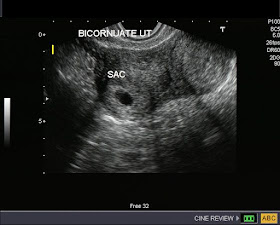

Bicornuate uterus with pregnancy

These transvaginal sonographic images show a bicornuate uterus with an early gestation sac in the right horn (cornu). Ultrasound images also show decidual tissue in the left horn. These patients can have normal pregnancy to full term, but must be carefully followed, as some may undergo a miscarriage.

Images courtesy of Dr. Jaydeep Gandhi, Mumbai, India.